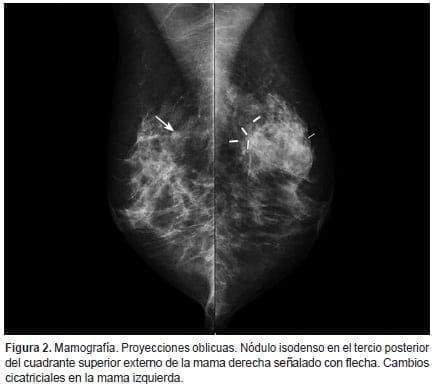

En 2018, presentó lesión mamaria palpable que motivó su consulta. En la mamografía se evidenció un nódulo isodenso en el tercio posterior del cuadrante superior externo de la mama derecha, y en la mama izquierda se observaron cambios postquirúrgicos debido al antecedente descrito (figuras 1 y 2). Se consideró BI-RADS 0 en la mamografía, por lo que se realizó una ecografía mamaria en la que se delimitó un nódulo hipoecoico de 6,8 x 3,5 mm, ubicado en el cuadrante superior externo de la mama derecha; lesión bien definida con eje mayor paralelo a la piel, sin efecto acústico posterior, sin señal Doppler color y de consistencia dura a la elastografía (figura 3), con aspecto imaginológico probablemente benigno, por lo que se consideró un BI-RADS 3 ecográfico, y se procedió a realizar una biopsia por trucut.